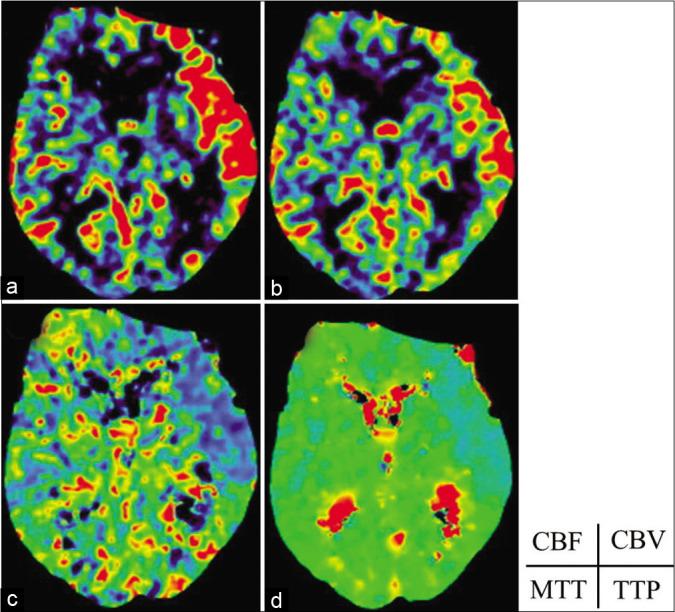

We report the case study of an 89-year-old man with CSDH who presented with the right hemiparesis. He underwent burr hole surgery with a closed-drainage system. A computed tomography (CT) scan conducted the following day demonstrated an acute intraventricular hemorrhage and hyperperfusion of the ipsilateral hemisphere.

This is a rare case of an acute hematoma in the ventricle following drainage of a CSDH. The likely mechanism of this intraventricular hemorrhage could be that the drainage of the hematoma produced a movement of the ventricle and hemisphere accompanied by hyperperfusion.

我们报告一例89岁患有CSDH的男性病例,该患者出现右侧偏瘫。他接受了带闭式引流系统的钻孔手术。术后第二天进行的计算机断层扫描(CT)显示急性脑室内出血及同侧半球血流灌注增加。

这是一例CSDH引流术后脑室急性血肿的罕见病例。这种脑室内出血的可能机制可能是血肿引流导致脑室和半球移动并伴有血流灌注增加。